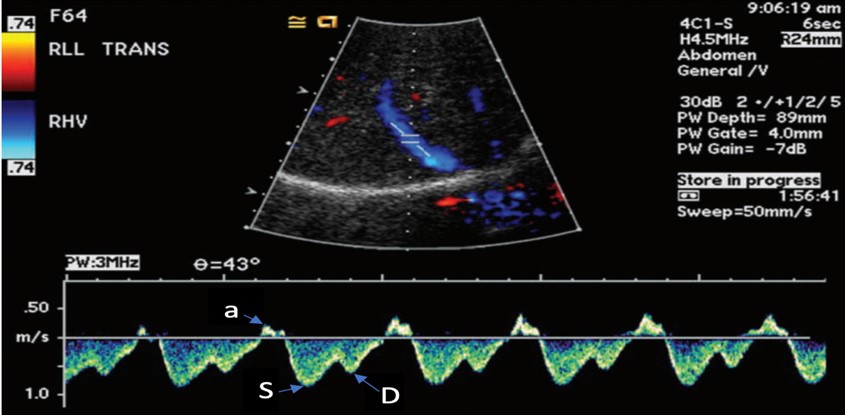

Figure 2. Normal hepatic vein Doppler (S>D wave)7

a= atrial kick

S= atrial systolic filling

D= atrial diastolic filling

The venous flow within the hepatic veins can be best thought of as a central venous pressure (CVP) tracing from the right atrium, reflecting the cardiac cycle of the right heart. Understanding this, the hepatic venous doppler waveform helps not only in the evaluation of venous congestion but also right heart function. The typical CVP tracing reveals an atrial kick, followed by systolic and diastolic filling of the atrium. A normal hepatic venous doppler will reveal a retrograde “a” wave followed by two antegrade “S” and “D” waves, as seen in Figure 2. A normal waveform consists of a relatively small a wave with the S wave larger than the following D wave (S>D), as a there is greater primary venous flow into the atrium during systole. As the venous system becomes engorged, the S wave becomes smaller relative to the D wave (S<D), due to a physiologic change from primarily systolic filling to a relative increase in passive diastolic filling of the heart (Figure 6A). As congestion continues, there is S wave reversal as seen in Figure 6B. The relative doppler flows noted in these tracings can thus help determine whether the heart is providing sufficient forward flow to prevent further venous engorgement, as well as help in the identification of right heart lesions, such as tricuspid regurgitant flows. Regurgitant flows may affect the pressures that are placed on the venous system. As such, hepatic vein flows can provide critical information about how the heart functions in response to increased venous congestion and determine when we have strained the heart to a point where it may benefit from de-resuscitation.